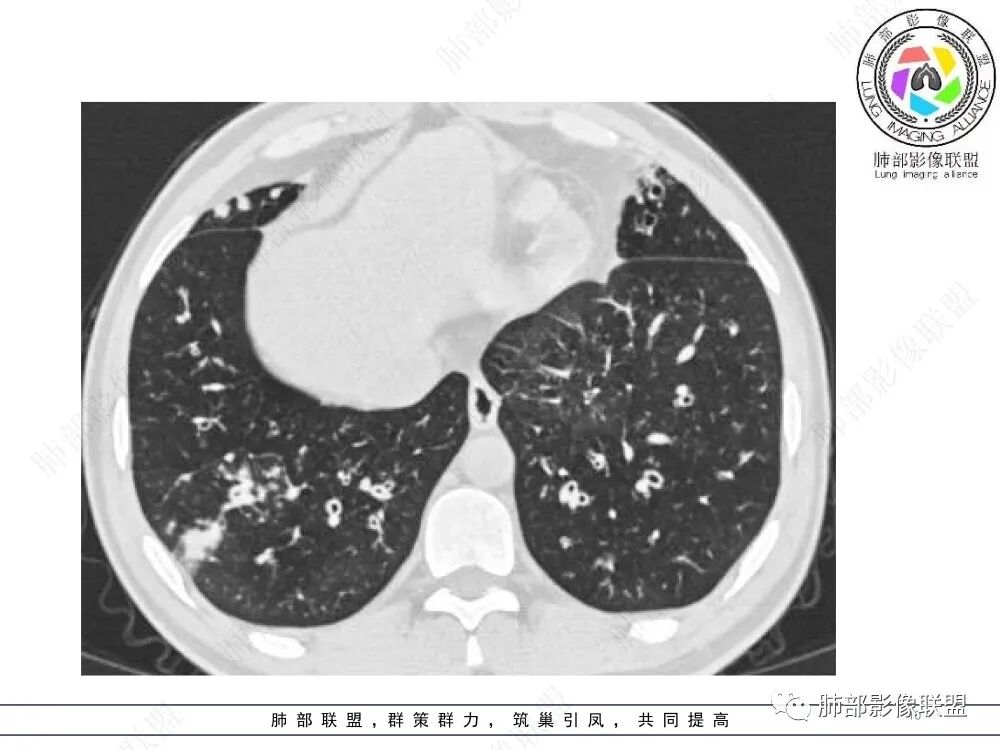

肺部影像联盟晨读病例肺气肿,多发气管壁增厚,片状影,符合气道分布,考虑气道侵袭性曲霉菌病。

支气管壁增厚,局部扩张,伴多发结节,痰栓!首先考虑曲霉!鉴别结核。

两肺多发弥漫性腺泡结节,支气管壁增厚,抗炎治疗后病变范围较前进展,沿支气管血管束分布,两肺见多发树芽及增厚扩张支气管,以右中叶及左上叶舌段为著,年轻患者,慢性病史,扩张支气管周围肺野未见肉芽肿性病变,抗炎治疗无效可排除诺卡及铜绿感染,综合分析首选NTM,其次气道侵袭性曲霉。

两肺支气管壁增厚,散在斑片状及树芽状影,抗炎治疗后病变范围进展,沿支气管血管束分布,两肺多发结节、树芽、实变及囊腔影,年轻患者,慢性病史,肺气肿背景,考虑气道侵袭性曲霉,鉴别NTM+铜绿。

两肺广泛支气管轻度扩张及管壁增厚,厚薄稍不均,累及叶段支气管,周围见散在斑片状密度增高性,部分实变,边缘模糊,下叶为著。考虑炎症,首先气道侵袭性曲霉,ntm待排。

晨读:最关键的有三点:1、临床表现及病史:35岁,男性,慢性刺激性咳嗽2月,吸烟史17年,没有糖尿病和其他免疫缺陷病史。这儿应该隐瞒了关键的吸入环节,存在大量曲霉孢子的工作环境没给。2、第一次影像改变:广泛的支扩,支气管壁增厚,多发的树芽,部分区域已经伴有支气管周围的渗出,少量实变。3、20多天后复查的影像,原有支扩,支气管壁增厚基础上的大量渗出,实变,伴结节,胸膜下累及。

35岁男性,慢性咳嗽2月余,吸烟17年。弥漫支气管壁增厚,腔部分增宽,部分狭窄,远端粘液栓,树芽征,边界模糊,抗炎无效。

6/13复查,外围出现斑片状实变影,周围GGO,从发病过程:支气管壁增厚,延续到小气道炎症,然后周围实变,首先气道来源病变,因为支气管壁的增厚,腔狭窄、扩张,其次病变广泛,几乎累及所有叶段,常规思路:气道侵袭性曲霉菌病;不除外努卡。与NTM鉴别,NTM其实支气管扩张为中型的多为中外带支气管扩张,中近端支气管改变不明显,这个中内带明显,而且早期是中内带为主。

2.胸部CT:两肺广泛的支扩,支气管壁增厚,多发的树芽影,部分伴有支气管周围的渗出,少量实变。不足一月复查,原有支扩、支气管壁增厚基础上伴有大量渗出,实变,结节,胸膜下累及。

3.综合分析:首先病灶沿支气管分布,呈树芽征及实变影,相应支气管壁广泛增厚,其次病变范围比较广泛,几乎累及所有叶段,这种表现常高度提示气道播散,经过对症抗感染治疗20多天后,胸部CT影像明显进展。符合IPA的进展表现。